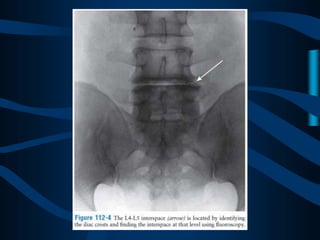

ABORDAJE

PARAESPINOSO

ABORDAJE CLASICO

DE DOS AGUJAS